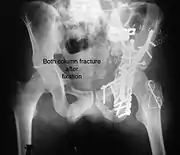

Posterior wall fracture fixed with screws and plate

High anterior column fracture after fixation with screws and plates

Transverse fracture fixed with screws and plate

Posterior column and wall fixed using screws and plates

Both column fracture after fixation with screws and plates